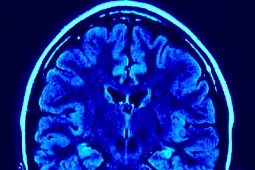

Strategmed dla guzów mózgu?

Nowy projekt zakłada wprowadzenie do leczenia substancji peptydowej w połączeniu z emiterami alfa. Chodzi o połączenie chemioterapii oraz promieniowania do podawania miejscowego, aby uniknąć powikłań ogólnych. Chemioterapeutyk uwalnia się w miejscu samego guza i łączy się z komórkami nowotworowymi oddziałując na nie. Emitery alfa to może być bizmut 213, aktyn lub astat. Różnią się one energią oraz czasem oddziaływania na zmianę nowotworową. Jego wartość nie przekroczy 12 mln zł.